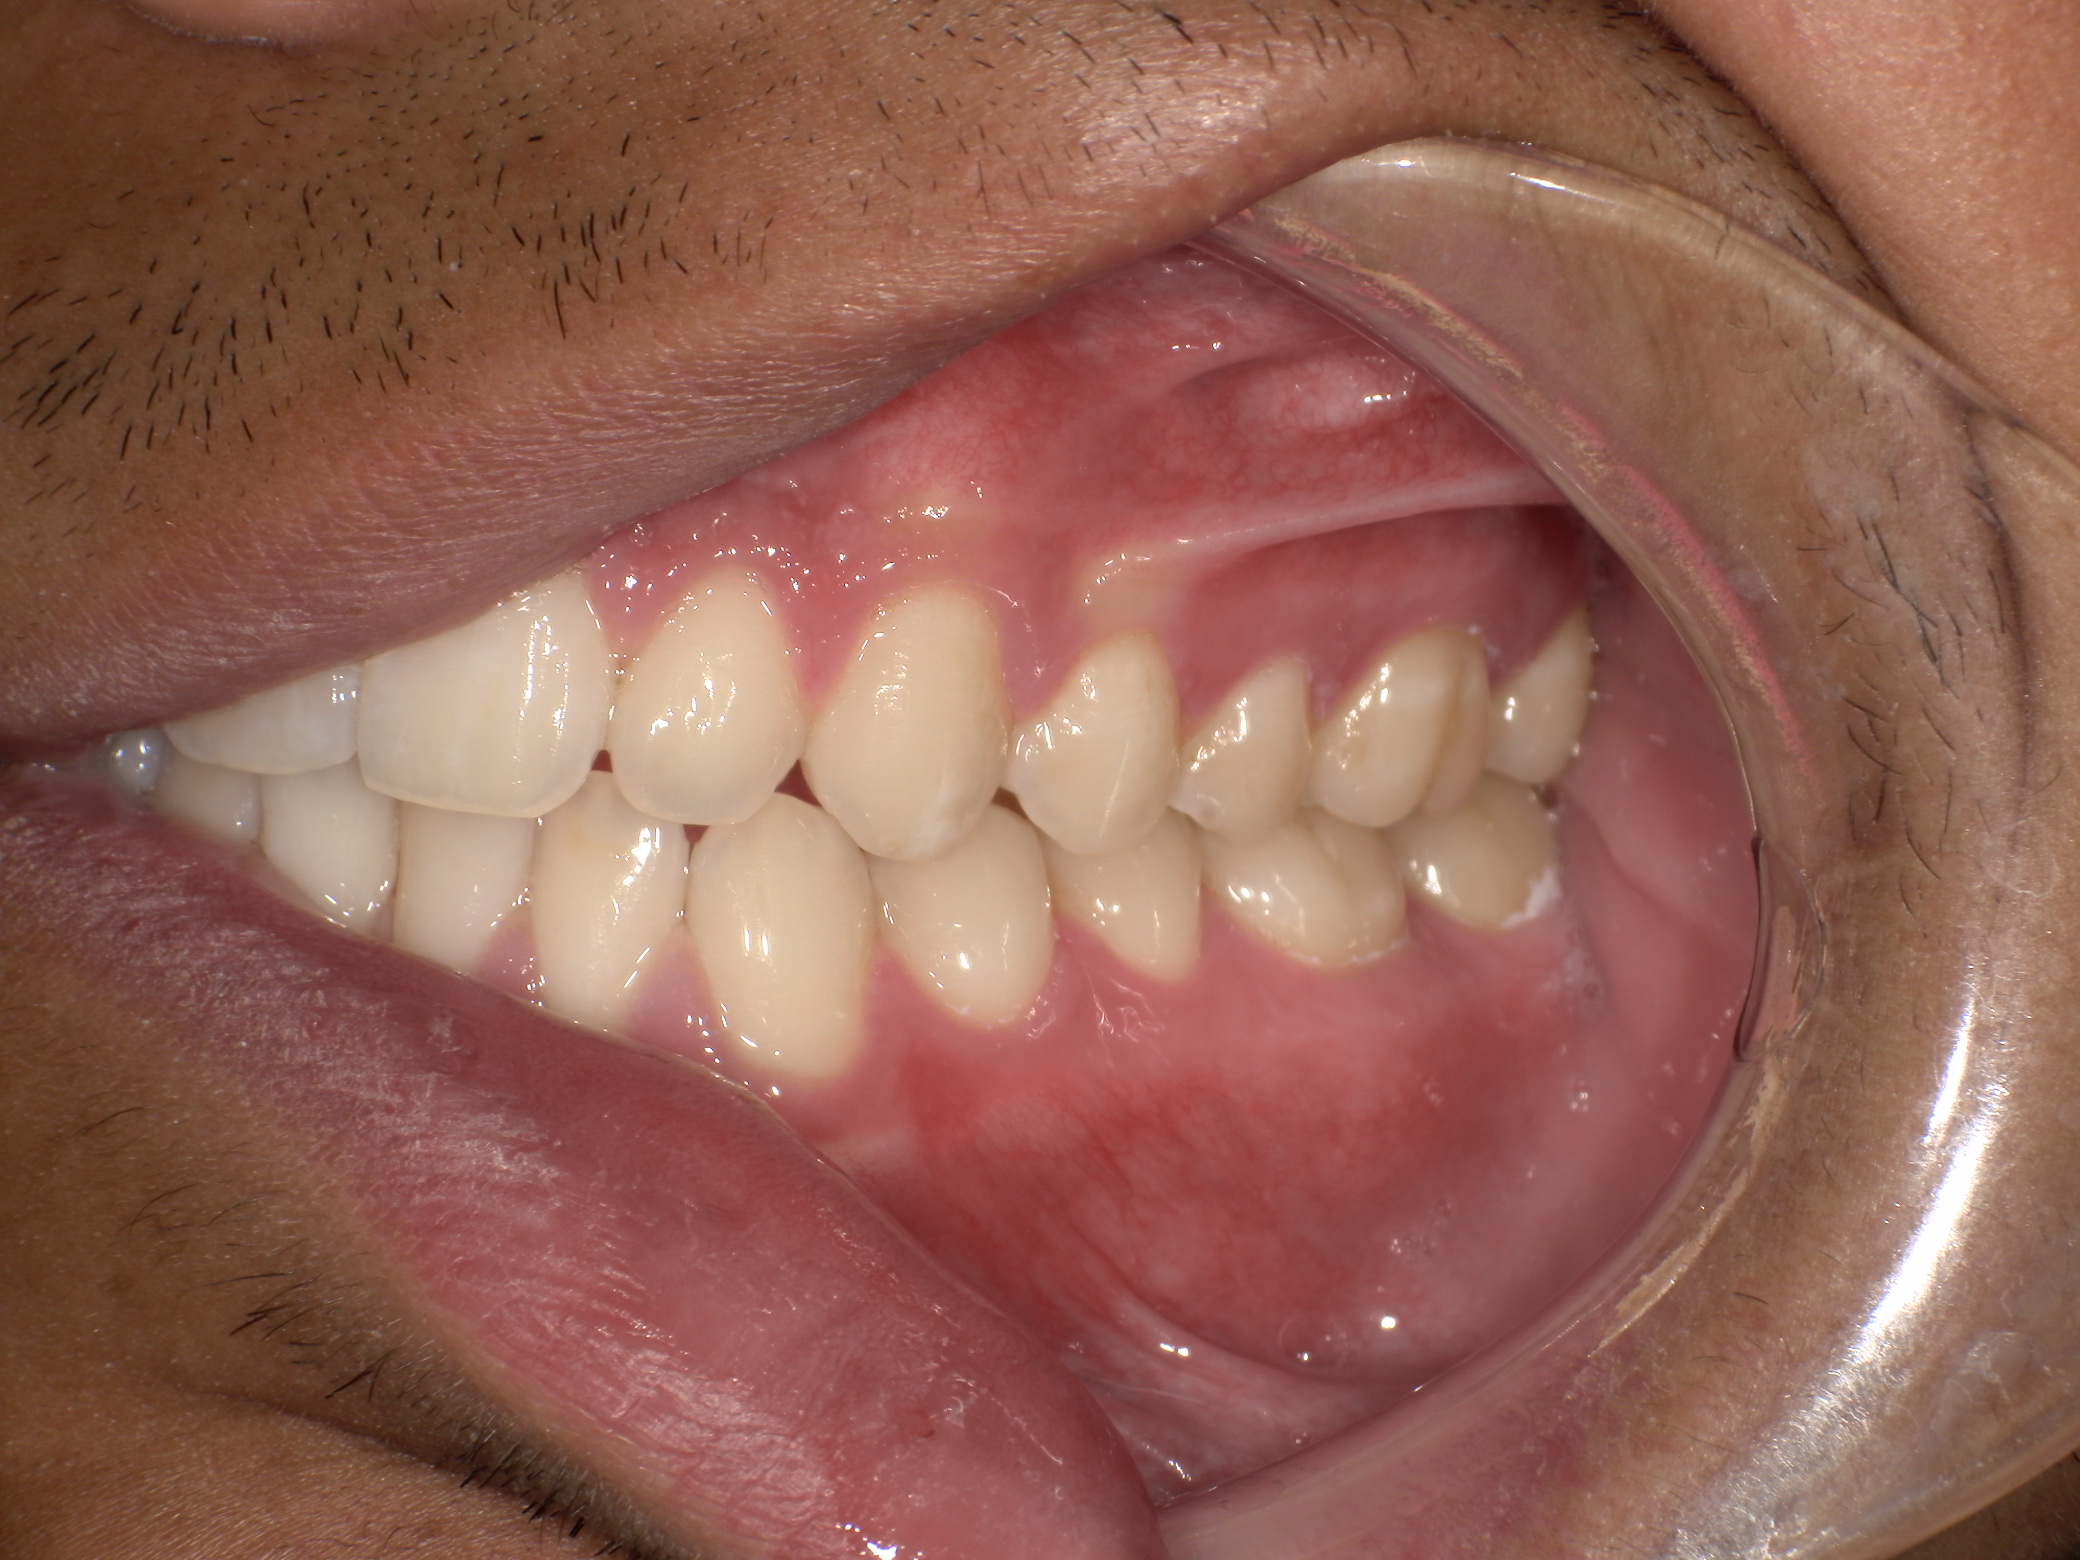

After your evaluation, the doctor reviews your results and explains how your airway structures are impacting your health. You’ll then receive a personalized plan that may include palatal expansion, aligners, or other therapies to optimize your health.